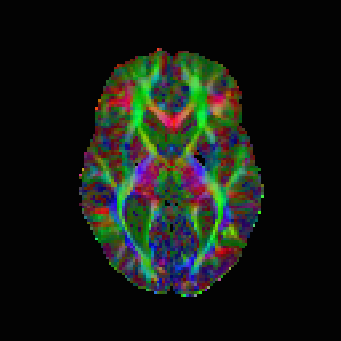

The results are in Table 2 and Figures 6–8, again with the first of the figures showing the colour-coded principal eigenvector of the reconstruction, the second showing the fractional anisotropy and principal eigenvectors, and the last one the errors in the latter two, in a colour-coded manner. Again, all plots are masked to represent only the non-zero region. In the figures, we concentrate on error bounds based on 95% confidence intervals, as the results for the 90% and 99% cases do not differ significantly according to Table 2.

This time, the linear approach (3.3) has best overall reconstruction (Frobenius PSNR), while the nonlinear approach (3.2) has clearly the best principal eigenvector angle reconstruction besides the regression, which does not seem entirely reliable regarding our regression-based pseudo-ground-truth. The constraints based approach (3.5), with 95% confidence intervals is, however, not far behind in terms of numbers. More detailed study of the corpus callosum in Figure 8 (small picture in picture) and Figure 7 however indicates a better reconstruction of this important region by the nonlinear approach. The constrained approach has some very short vectors there in the white region. Naturally, however, these results on the in vivo data should be taken with a grain of salt, as we have only a somewhat unreliable pseudo-ground-truth available for comparison purposes.

It shall also be investigated whether the error bounds approach needs to be combined with an alternative, novel, regulariser that would ameliorate the fractional anisotropy errors that the approach exhibits. It is important to note, however, that from the practical point of view, of using the reconstruction tensor field for basic tractography methods based solely on principal eigenvectors, these are not that critical. As pointed out by one of the reviewers, the situation could differ with more recent geodesic tractography methods [hao2011adaptive, schultz2014novel, fuster2016adjugate] employing the full tensor. We provide basic principal eigenvector tractography results for reference in Figure 9, without attempting to extensively interpret the results. It suffices to say that the results look comparable. With this in sight, the error bounds approach produces a very good reconstruction of the direction of the principal eigenvectors, although we saw some problems with the magnitude within the corpus callosum.